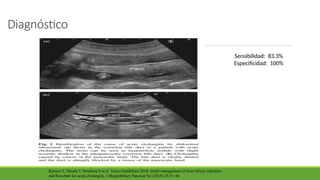

Diagnóstico

Sensibilidad: 83.3%

Especificidad: 100%

Kimura Y, Takada T, Strasberg S et al. Tokyo Guidelines 2018: initial management of acute biliary infection